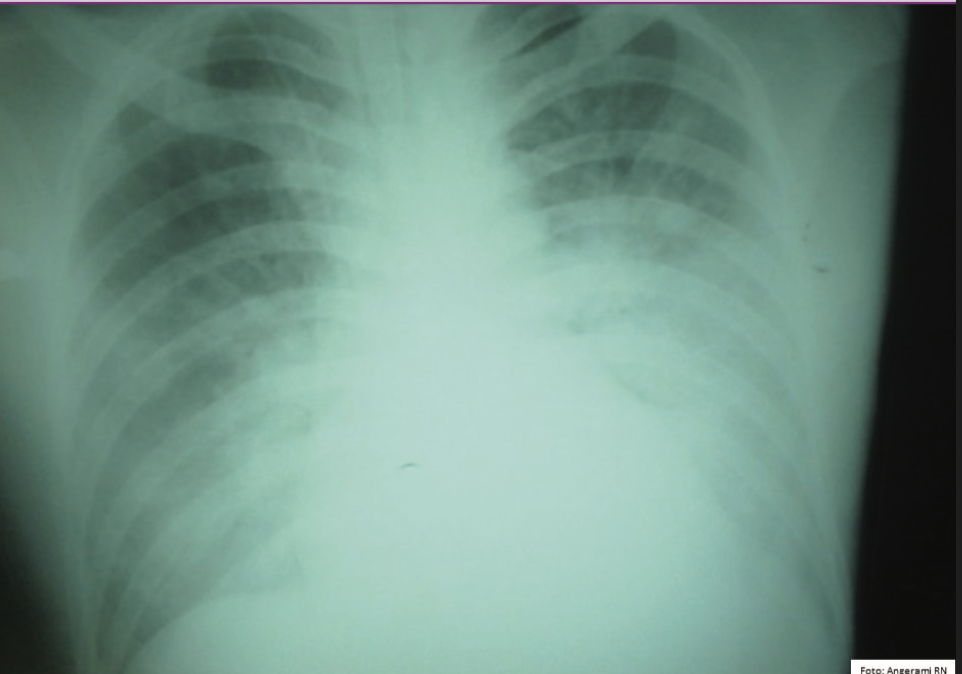

DIP: Febre Maculosa

Acometimento pulmonar

A

Tosse, infiltrado alveolar e pneumonia intersticial

Forma fulminante pode evoluir a óbito em 6 dias